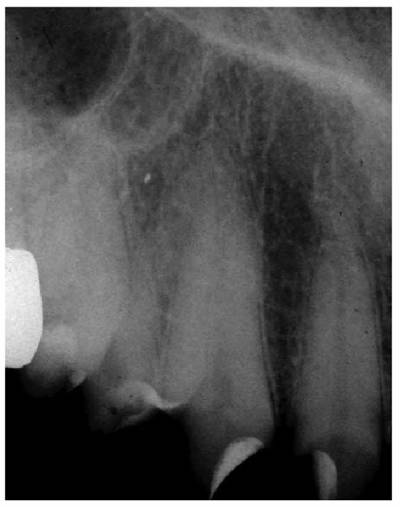

Precementation Radiographs

Prior to cementation, Yamada (personal communication, 2001) re-radiographs the

prepared teeth (Figures 19-25A

and B).

These images check the pulpal, periapical, and periodontal status of the teeth.

Also, the radiographs, unencumbered by the presence of the metal castings,

provide a chamber/canal road map record if the tooth requires endodontics in

the future. This may appear pessimistic, but Arens and Chivian reported that

over 40% of teeth requiring root canal therapy are crowned.4 Prior

knowledge of the size, location, and direction of the chamber and the canal will

reduce the possibility of (1) crown damage during access opening, (2) lost time

searching for the canal orifice, (3) perforations of the chamber or the canal

because of disorientation, (4) natural core elimination by gutting, (5) crown

dislodgment, and (6) sufficient destruction to alter the situation and require

corrective surgery. Each of these iatrogenic possibilities reduces the

prognosis and jeopardizes the tooth's reliability as an abutment.

Figure 19-25A and B: Precementation radiographs provide a road map to the canals if endodontic therapy is necessary after cementation of the castings. (Radiographs courtesy of Dr. Henry Yamada.)